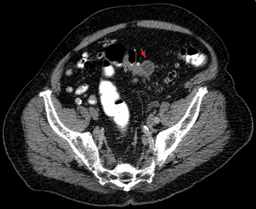

*Image from Hellerhoff, CC BY-SA 3.0 <https://creativecommons.org/licenses/by-sa/3.0>, via Wikimedia Commons